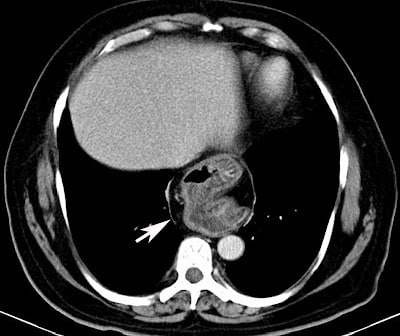

- CT ΘΩΡΑΚΟΣ–ΑΝΩ ΚΟΙΛΙΑΣ

- Παραοισοφαγική κήλη με επιπλοκές (συστροφή, απόφραξη, ισχαιμία), οξεία εικόνα θώρακα/κοιλίας

- Αναπνευστικά συμπτώματα/εισρόφηση, διαφορική διάγνωση πόνου στο στήθος

- +/− CT Θώρακος–Άνω Κοιλίας αν υποψία παραοισοφαγικής κήλης/συστροφής/ισχαιμίας